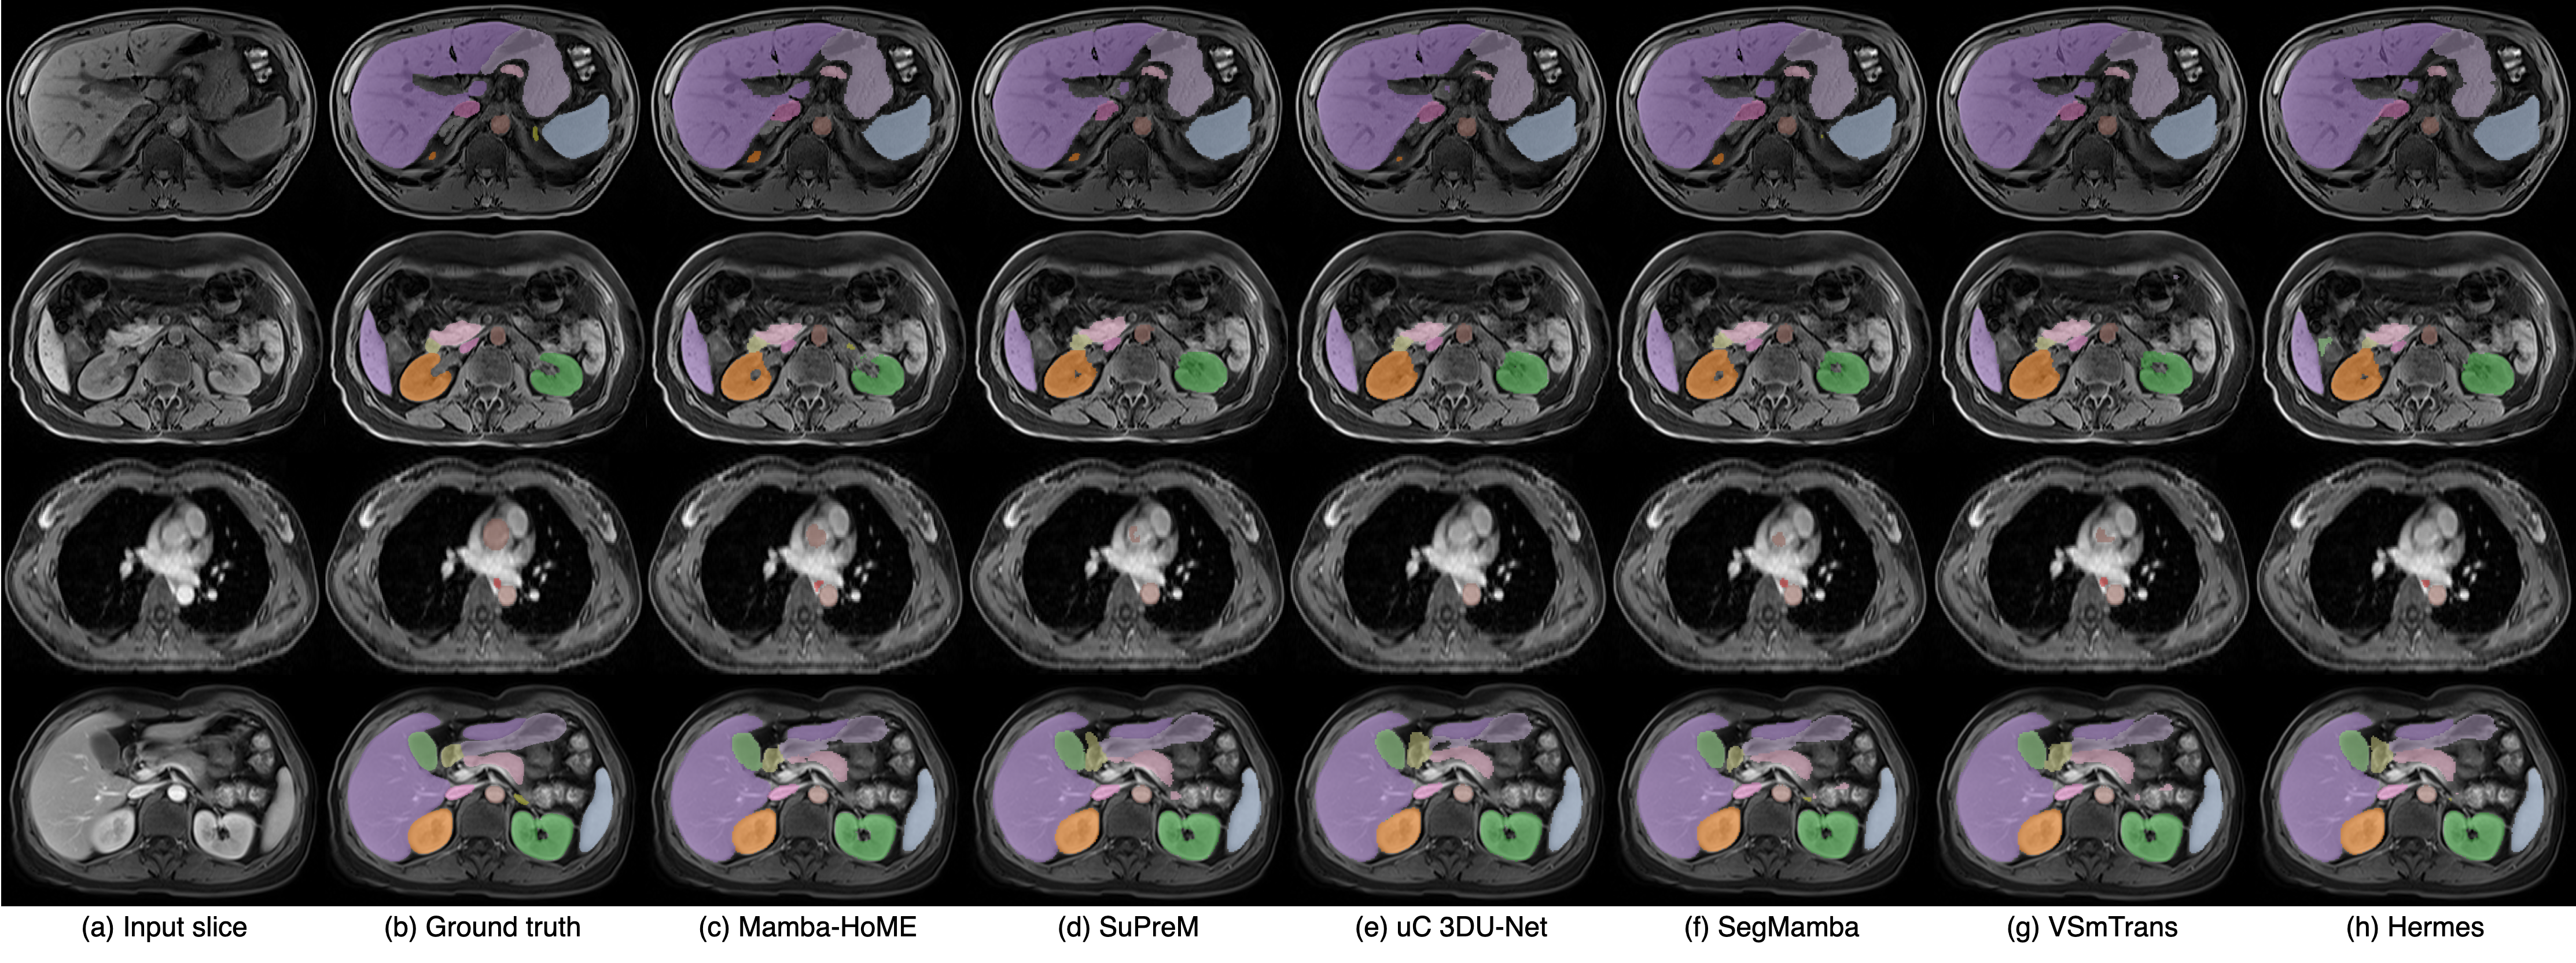

Qualitative results. Figure 2 presents a qualitative comparison of our proposed Mamba-HoME method against the five top-performing baselines across three primary 3D medical imaging modalities: CT, MRI, and US. These modalities exhibit different organ contrasts, noise levels, and resolutions. Mamba-HoME demonstrates consistent improvements in segmentation quality across these scenarios. In the first row, it effectively handles small and closely located structures, showing precise boundary delineation while reducing common artifacts seen in baseline predictions. The second row highlights its capability to accurately segment organs of various shapes and sizes, even under low image quality conditions, with reduced susceptibility to over- or under-segmentation. The third row illustrates Mamba-HoME’s robustness in handling noisy and low-resolution data, maintaining clear and anatomically accurate boundaries.

Figure 2: Qualitative segmentation results from top to bottom: CT, MRI, and 3D US. From left to right, each column shows the input slice, ground truth, the proposed Mamba-HoME, and the five next best-performing methods.